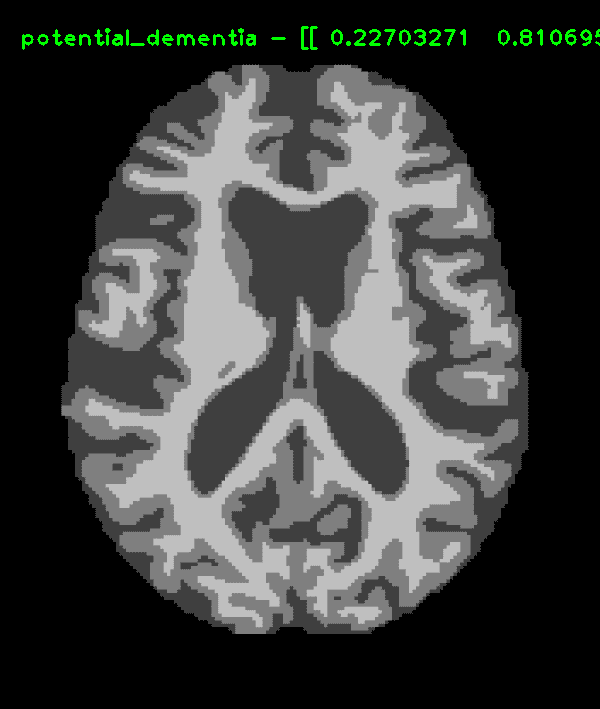

I used OASIS's public archive of cross-sectional MRI data to build a convolutional neural network in Keras using a pre-trained model (transfer learning with VGG-16) that could detect signs of dementia with either a multi-class or binary classification model. The binary classifier had a ~60% accuracy rate (consistent with different variations of training / test data) with a 13% false positive rate.

Due to the limited amount of data available, the current models in the repository are trained for only binary classification, to detect either no dementia (nondemented) or potential dementia (possibly demented), although you can train the tertiary and quaternary models with the same script. The multi-label classifications also pave the possibility of discovering patterns in brain scans that could be linked to the progression of dementia over time, potentially leading into the basics of a scientific model which can diagnose dementia long before symptoms show.

In the current models, the FSLSEG classifier could identify 3 out of 5 (+-1) potentially demented individuals when shown new MRIs (an accuracy rate of ~60%). Of new nondemented patients shown, 2 (+-2) out of 16 were misidentified as false positives (~13%), with the other 14 receiving the correct 'normal' diagnosis. Both FSLSEG and RAW classifiers showed similar results and accuracies with consistency. These results were taken from an average of multiple testing done with different selections of the data randomly chosen for training, testing, and validation (only 5-7 demented MRIs were reserved for testing each time, as the training or validation sample sizes would be too small).